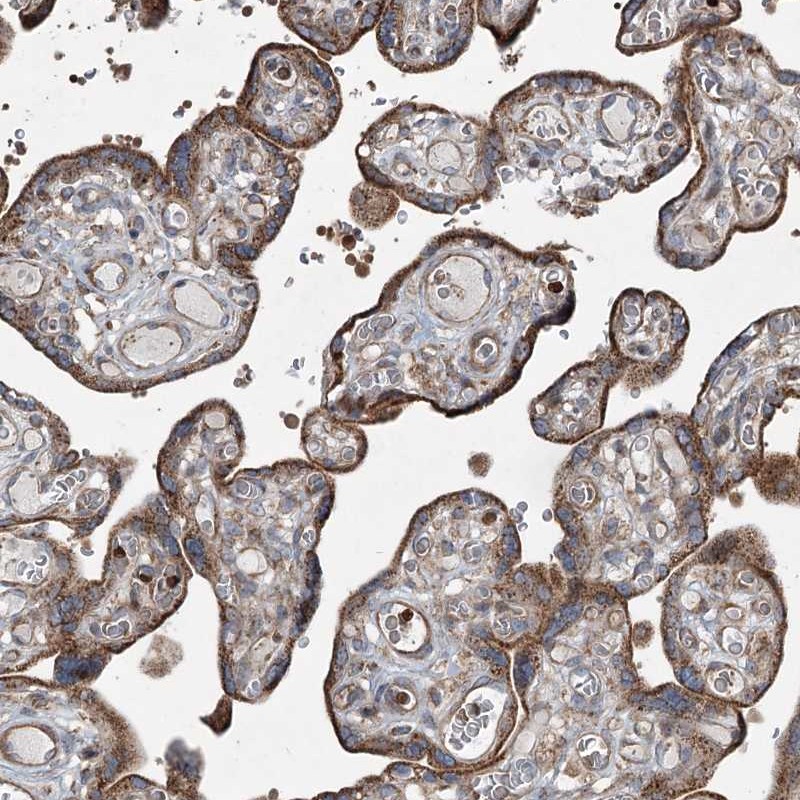

Immunohistochemical staining of human placenta shows cytoplasmic positivity in trophoblastic cells.